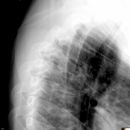

BWK 5 Fraktur